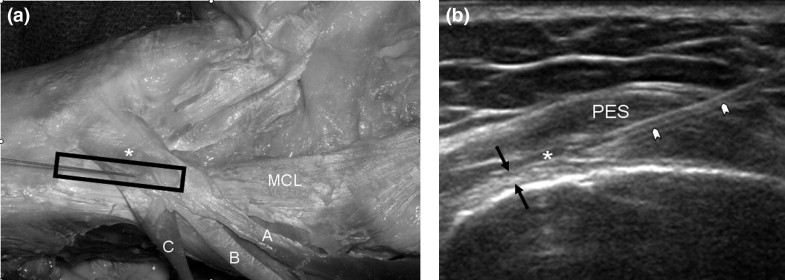

運動傷害 - 鵝掌肌腱炎 Pes anserinus tendinitis / Bursitis 取得連結 Facebook X Pinterest 以電子郵件傳送 其他應用程式 6月 03, 2021 鵝掌肌腱炎Pes anserinus tendinitis 內側膝蓋痛膝蓋內側三指下位置可能腫起解剖 - 鵝掌由三條肌腱組成,很像鵝掌得名Sartorius 縫匠肌Gracilis 股薄肌Semitendinous 半腱肌主要功能屈膝 knee flexion抵抗膝蓋外翻 Resist knee valgus受傷機轉肌腱炎過度膝蓋外翻 - 合併其他組織損傷 MCL, Medial meniscus滑液囊炎過度使用造成常見運動游泳 (蛙式踢腿) 跑步自行車治療冰敷口服藥 NSAID電療 Electrotherapeutic modality離心拉筋 eccentric stretching肌力訓練 Strenthening超音波注射 Sonoguided corticosteroid injection 參考資料. Brukner & Khan's Clinical Sports Medicine Vol.1, 5th edition 取得連結 Facebook X Pinterest 以電子郵件傳送 其他應用程式 留言